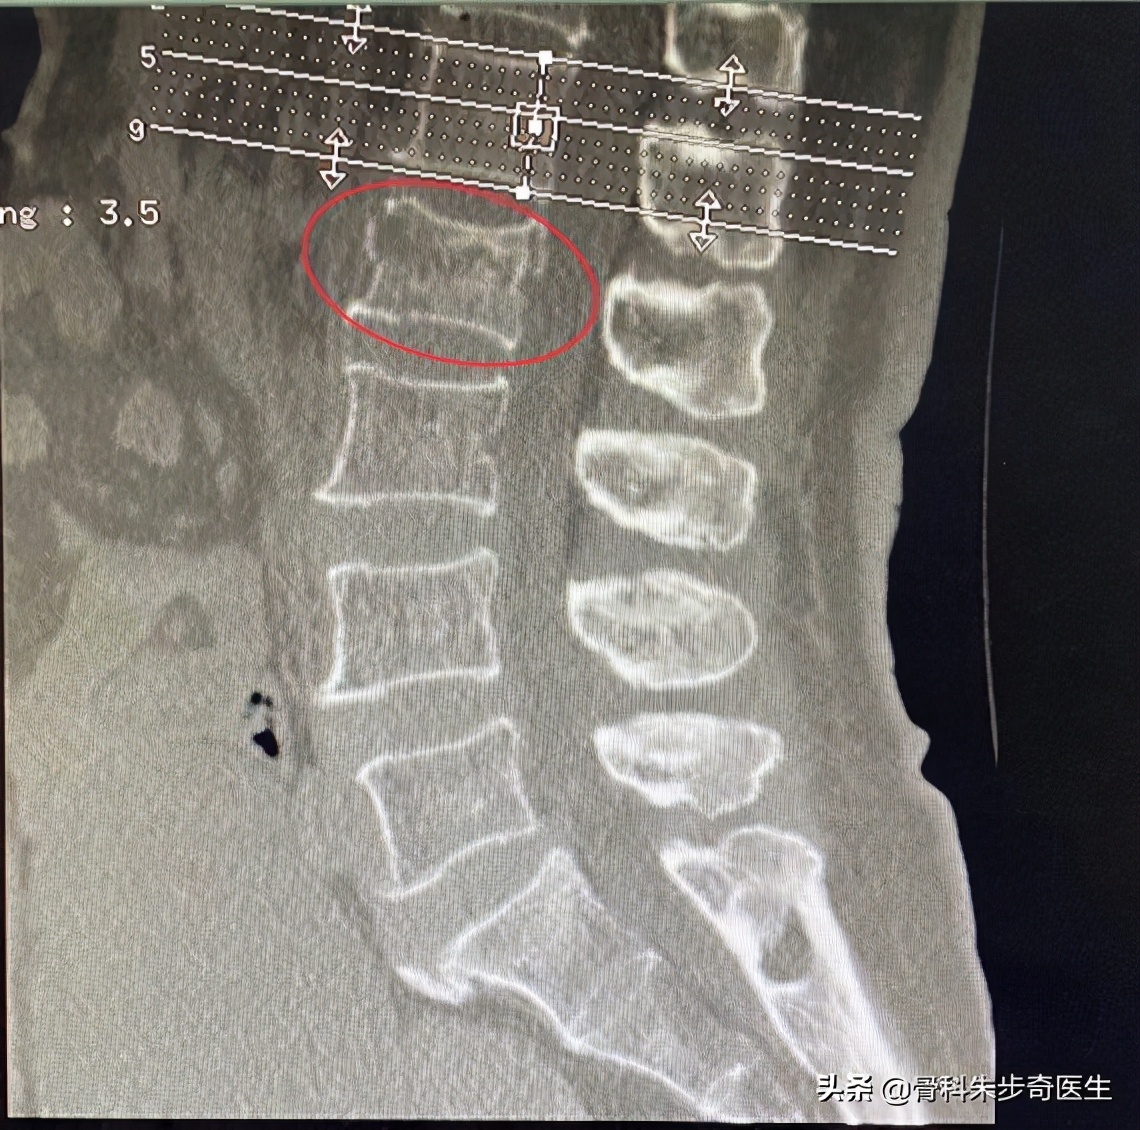

看到这个情况,首先要确定的是神经功能有没有问题,也就是神经到底损伤了没有,做了下查体,下肢的活动和感觉都没有问题,也没有肛门以及会阴区域的麻木感觉,这说明神经功能基本上是好的,但是还是不能掉以轻心,开了一个CT检查赶紧去做,结果很快出来了,片子及报告单如下:

从片子上可以看出来,她的腰2椎体骨折,所以就安排她住院了,40床。

这是腰2椎体,而画圈的部位就是腰椎后方的结构,这个结构是非常重要的结构,这里是否存在骨折是判断是否手术的比较关键的一点。